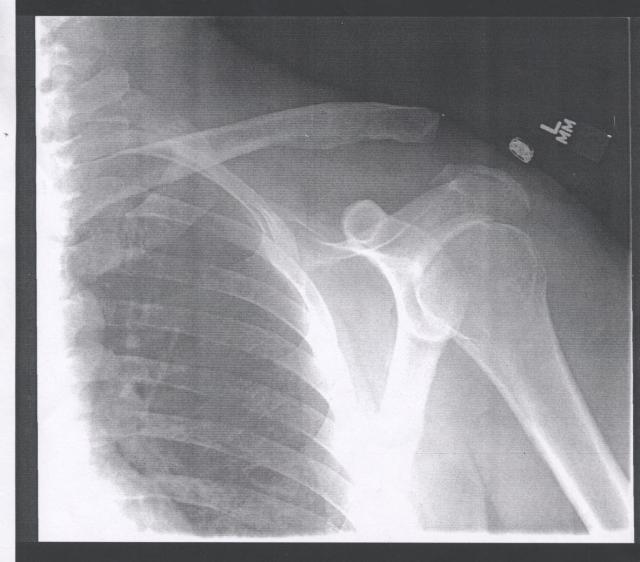

This is what happens when you get run over by a Chevy S10 while riding your motrorcycle home from work

And they REALLY screw you

Doc says I did a ‘bang-up’ job of tearing all 6 ligaments. As bad as it gets before things start going SNAP. He’s happy with the work and the prognosis is good. Screw should come out in CORRECTION – 3 MONTHS. Then a little more sling time and back to work. Golf game should be tuned up in time for The TYMI at Pebble next year.